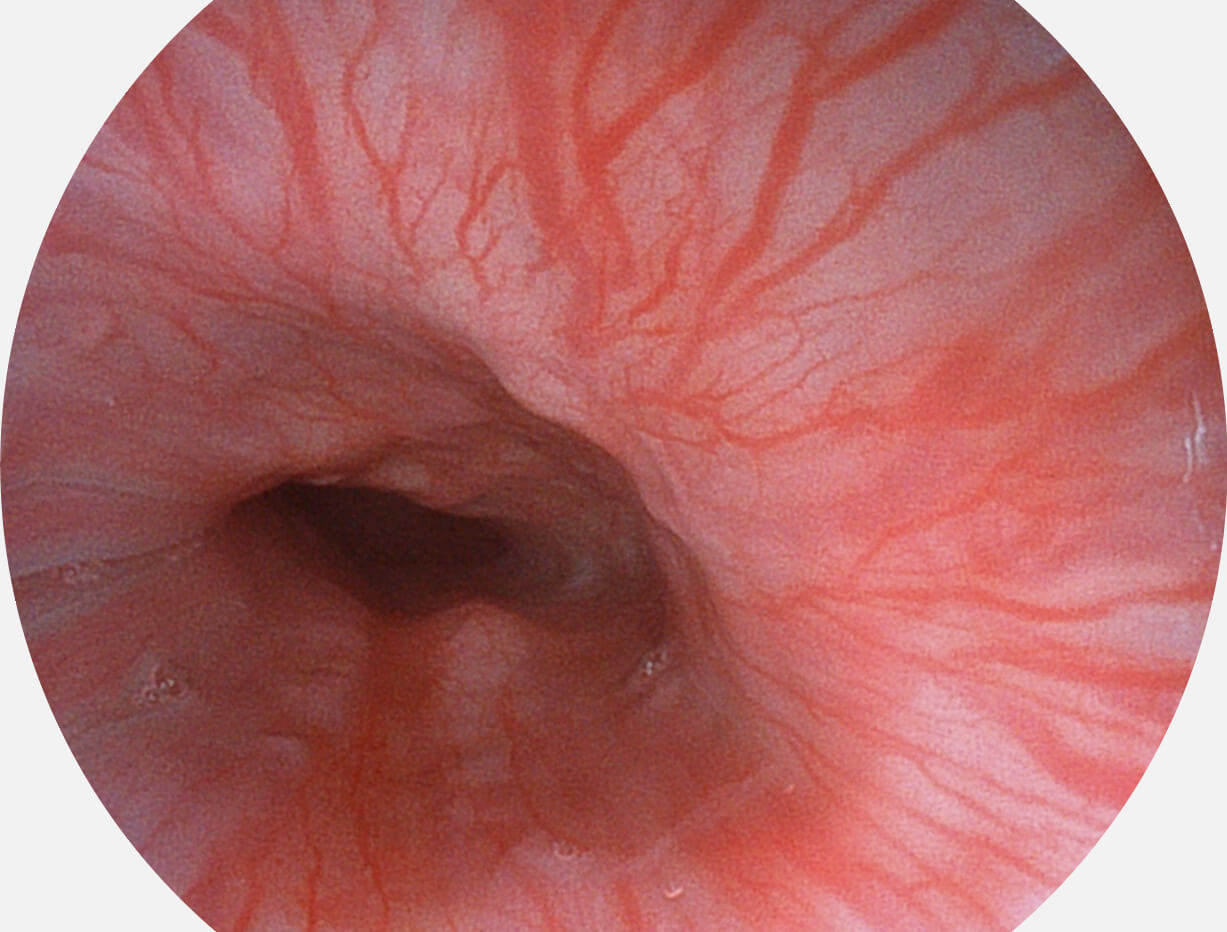

白光图像

白光图像

SFI图像

SFI图像

白光图像

白光图像

SFI图像

SFI图像

白光图像

白光图像

SFI图像

SFI图像